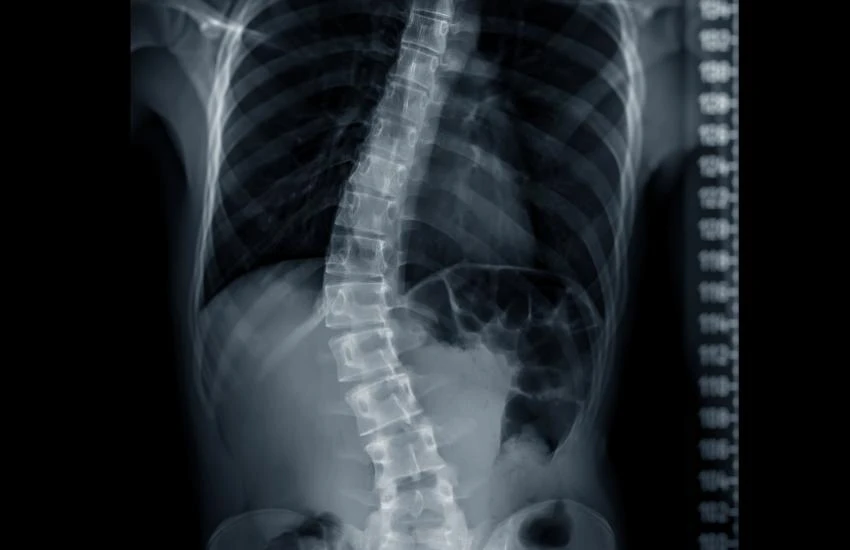

A escoliose é uma alteração da coluna vertebral que costuma surgir ou se intensificar durante a adolescência, fase marcada por crescimento acelerado e grandes mudanças corporais. O que muitas famílias não sabem é que a escoliose nem sempre provoca dor, e exatamente por isso pode passar despercebida por anos.

A escoliose é uma alteração tridimensional da coluna, caracterizada por:

•    desvio lateral da coluna

•    rotação das vértebras

•    mudanças no alinhamento global do tronco

Ela pode ter diferentes causas, mas a forma mais comum na adolescência é a escoliose idiopática, ou seja, sem uma causa única identificável.